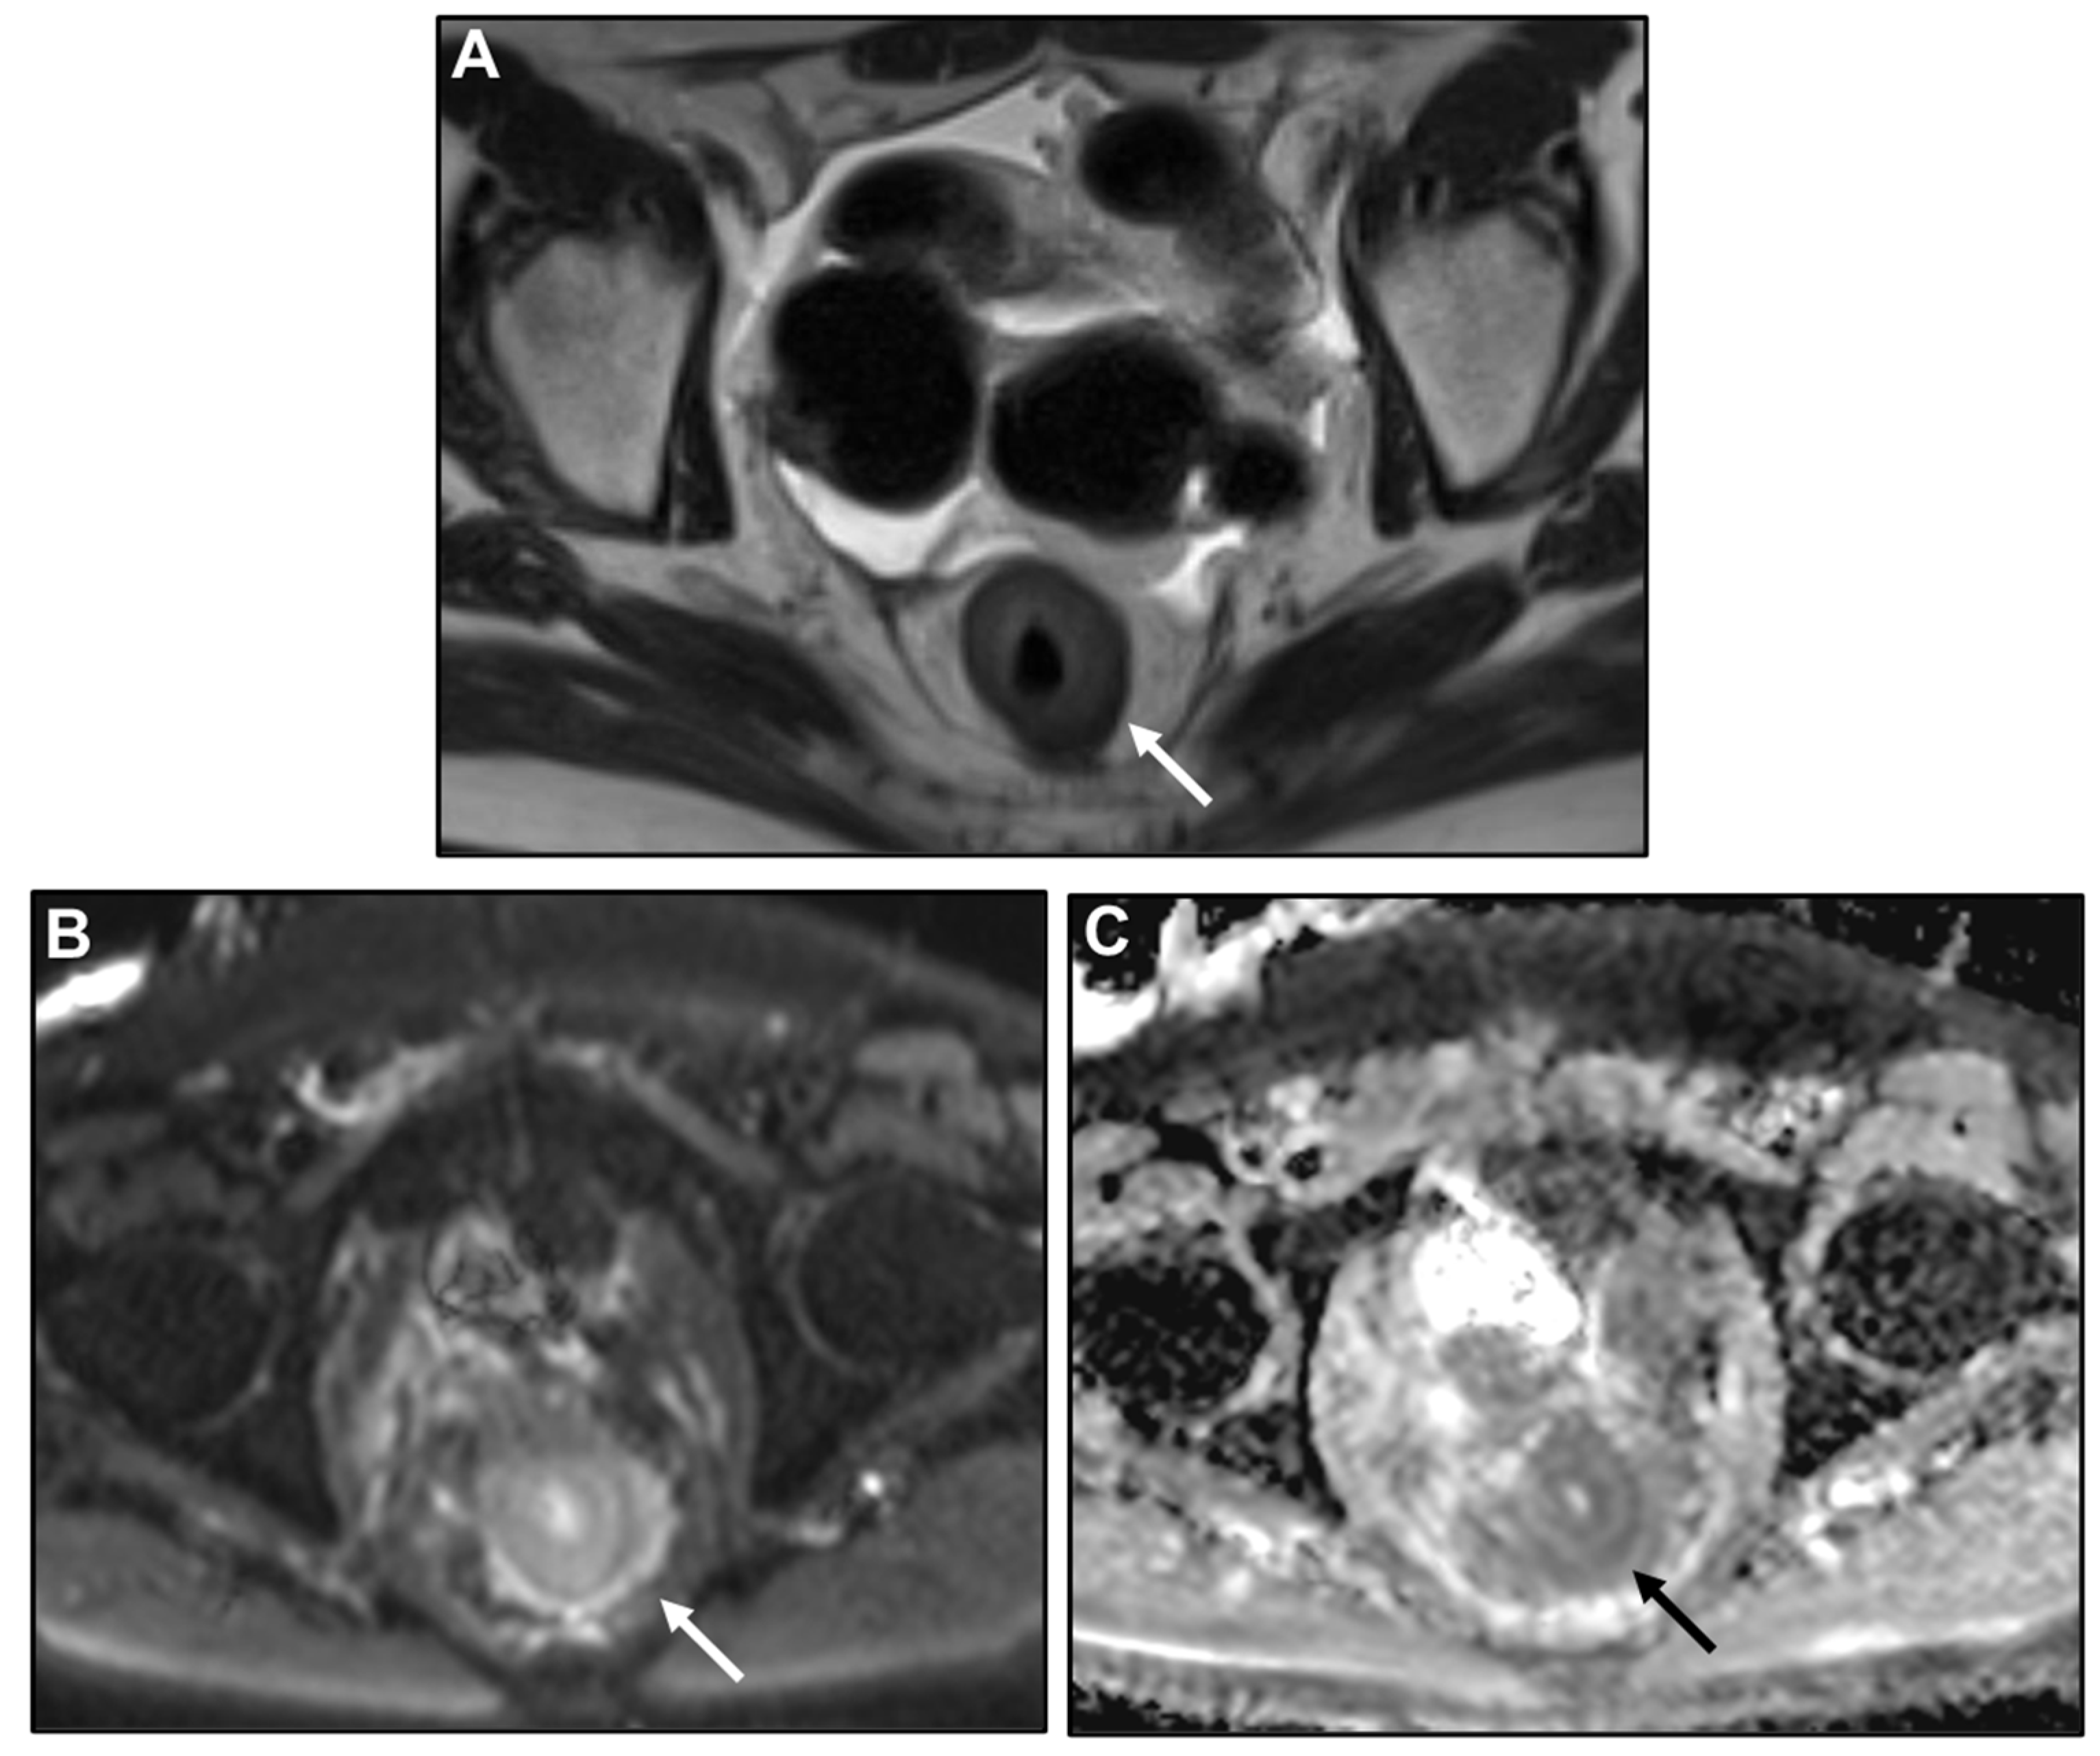

Presacral Fat Tissue and Rectovaginal Septum Infiltration and T2-Weighted Imaging (T2WI) Hypointense Extramural Tumour Component

- Lau, L.C.; Wee, B.; Wang, S.; Thian, Y.L. Metastatic breast cancer to the rectum: A case report with emphasis on MRI features. Medicine 2017, 96, e6739. [Google Scholar] [CrossRef] [PubMed]

- Rudralingam, V.; Dobson, M.J.; Pitt, M.; Stewart, D.J.; Hearn, A.; Susnerwala, S. MR imaging of linitis plastica of the rectum. AJR Am. J. Roentgenol. 2003, 181, 428–430. [Google Scholar] [CrossRef] [PubMed]

- Dresen, R.C.; Beets, G.L.; Rutten, H.J.T.; Engelen, S.M.E.; Lahaye, M.J.; Vliegen, R.F.A.; de Bruïne, A.P.; Kessels, A.G.H.; Lammering, G.; Beets-Tan, R.G.H. Locally advanced rectal cancer: MR imaging for restaging after neoadjuvant radiation therapy with concomitant chemotherapy. Part I. Are we able to predict tumor confined to the rectal wall? Radiology 2009, 252, 71–80. [Google Scholar] [CrossRef]